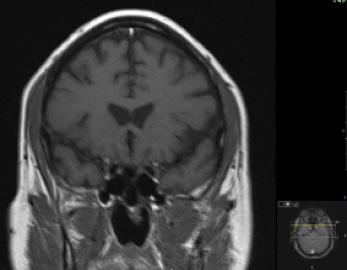

Figure 6. T1-weighted MRI scan, coronal section, with contrast, after surgical resection. No mass is present.

In the 2 years following surgery, most of this patient’s visual field defects resolved (Figure 7) even though his RNFL defects remained stable (Figure 8). Given his history of elevated IOP and a persistent RNFL-localizing inferior arcuate defect, he continued glaucoma medical therapy. He recently underwent bilateral cataract surgery, after which IOP decreased in each eye. At his last follow-up visit, UCVA was 20/20 OU, and IOP measured in the middle teens in each eye.